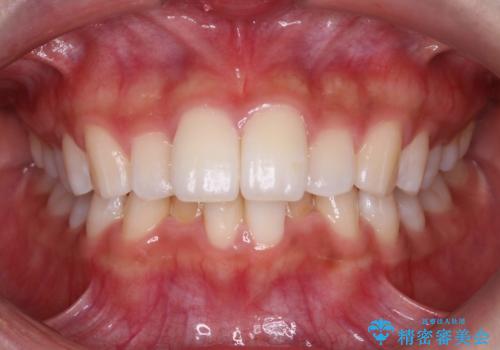

Invisalign インビザラインによる軽度なガタつきの改善

- 奥歯の位置関係はそこまで大きくいじらず、前歯群のみでガタつきの改善を計画しました

奥歯の位置関係に改善の余地はありますが、機能的に問題のない cusp to fossa の関係で咬めているため、前歯のガタつきを前歯のみで改善するというシンプルな計画で、短期間で治療を終了させました。